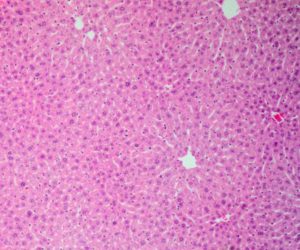

Alcohol-associated liver disease accounts for half of liver disease-related deaths, and its rates are rising worldwide. The main characteristic of alcohol-associated liver disease is excess fat in liver cells. Without proper intervention, it may progress to life-threatening conditions such as cirrhosis and liver carcinoma.

Hepatic stellate cells are calm in the normal liver, but they secrete collagen when activated. The effect is a very stiff and thick scaffold of scar tissue called extracellular matrix. Collagen is one part of this matrix.